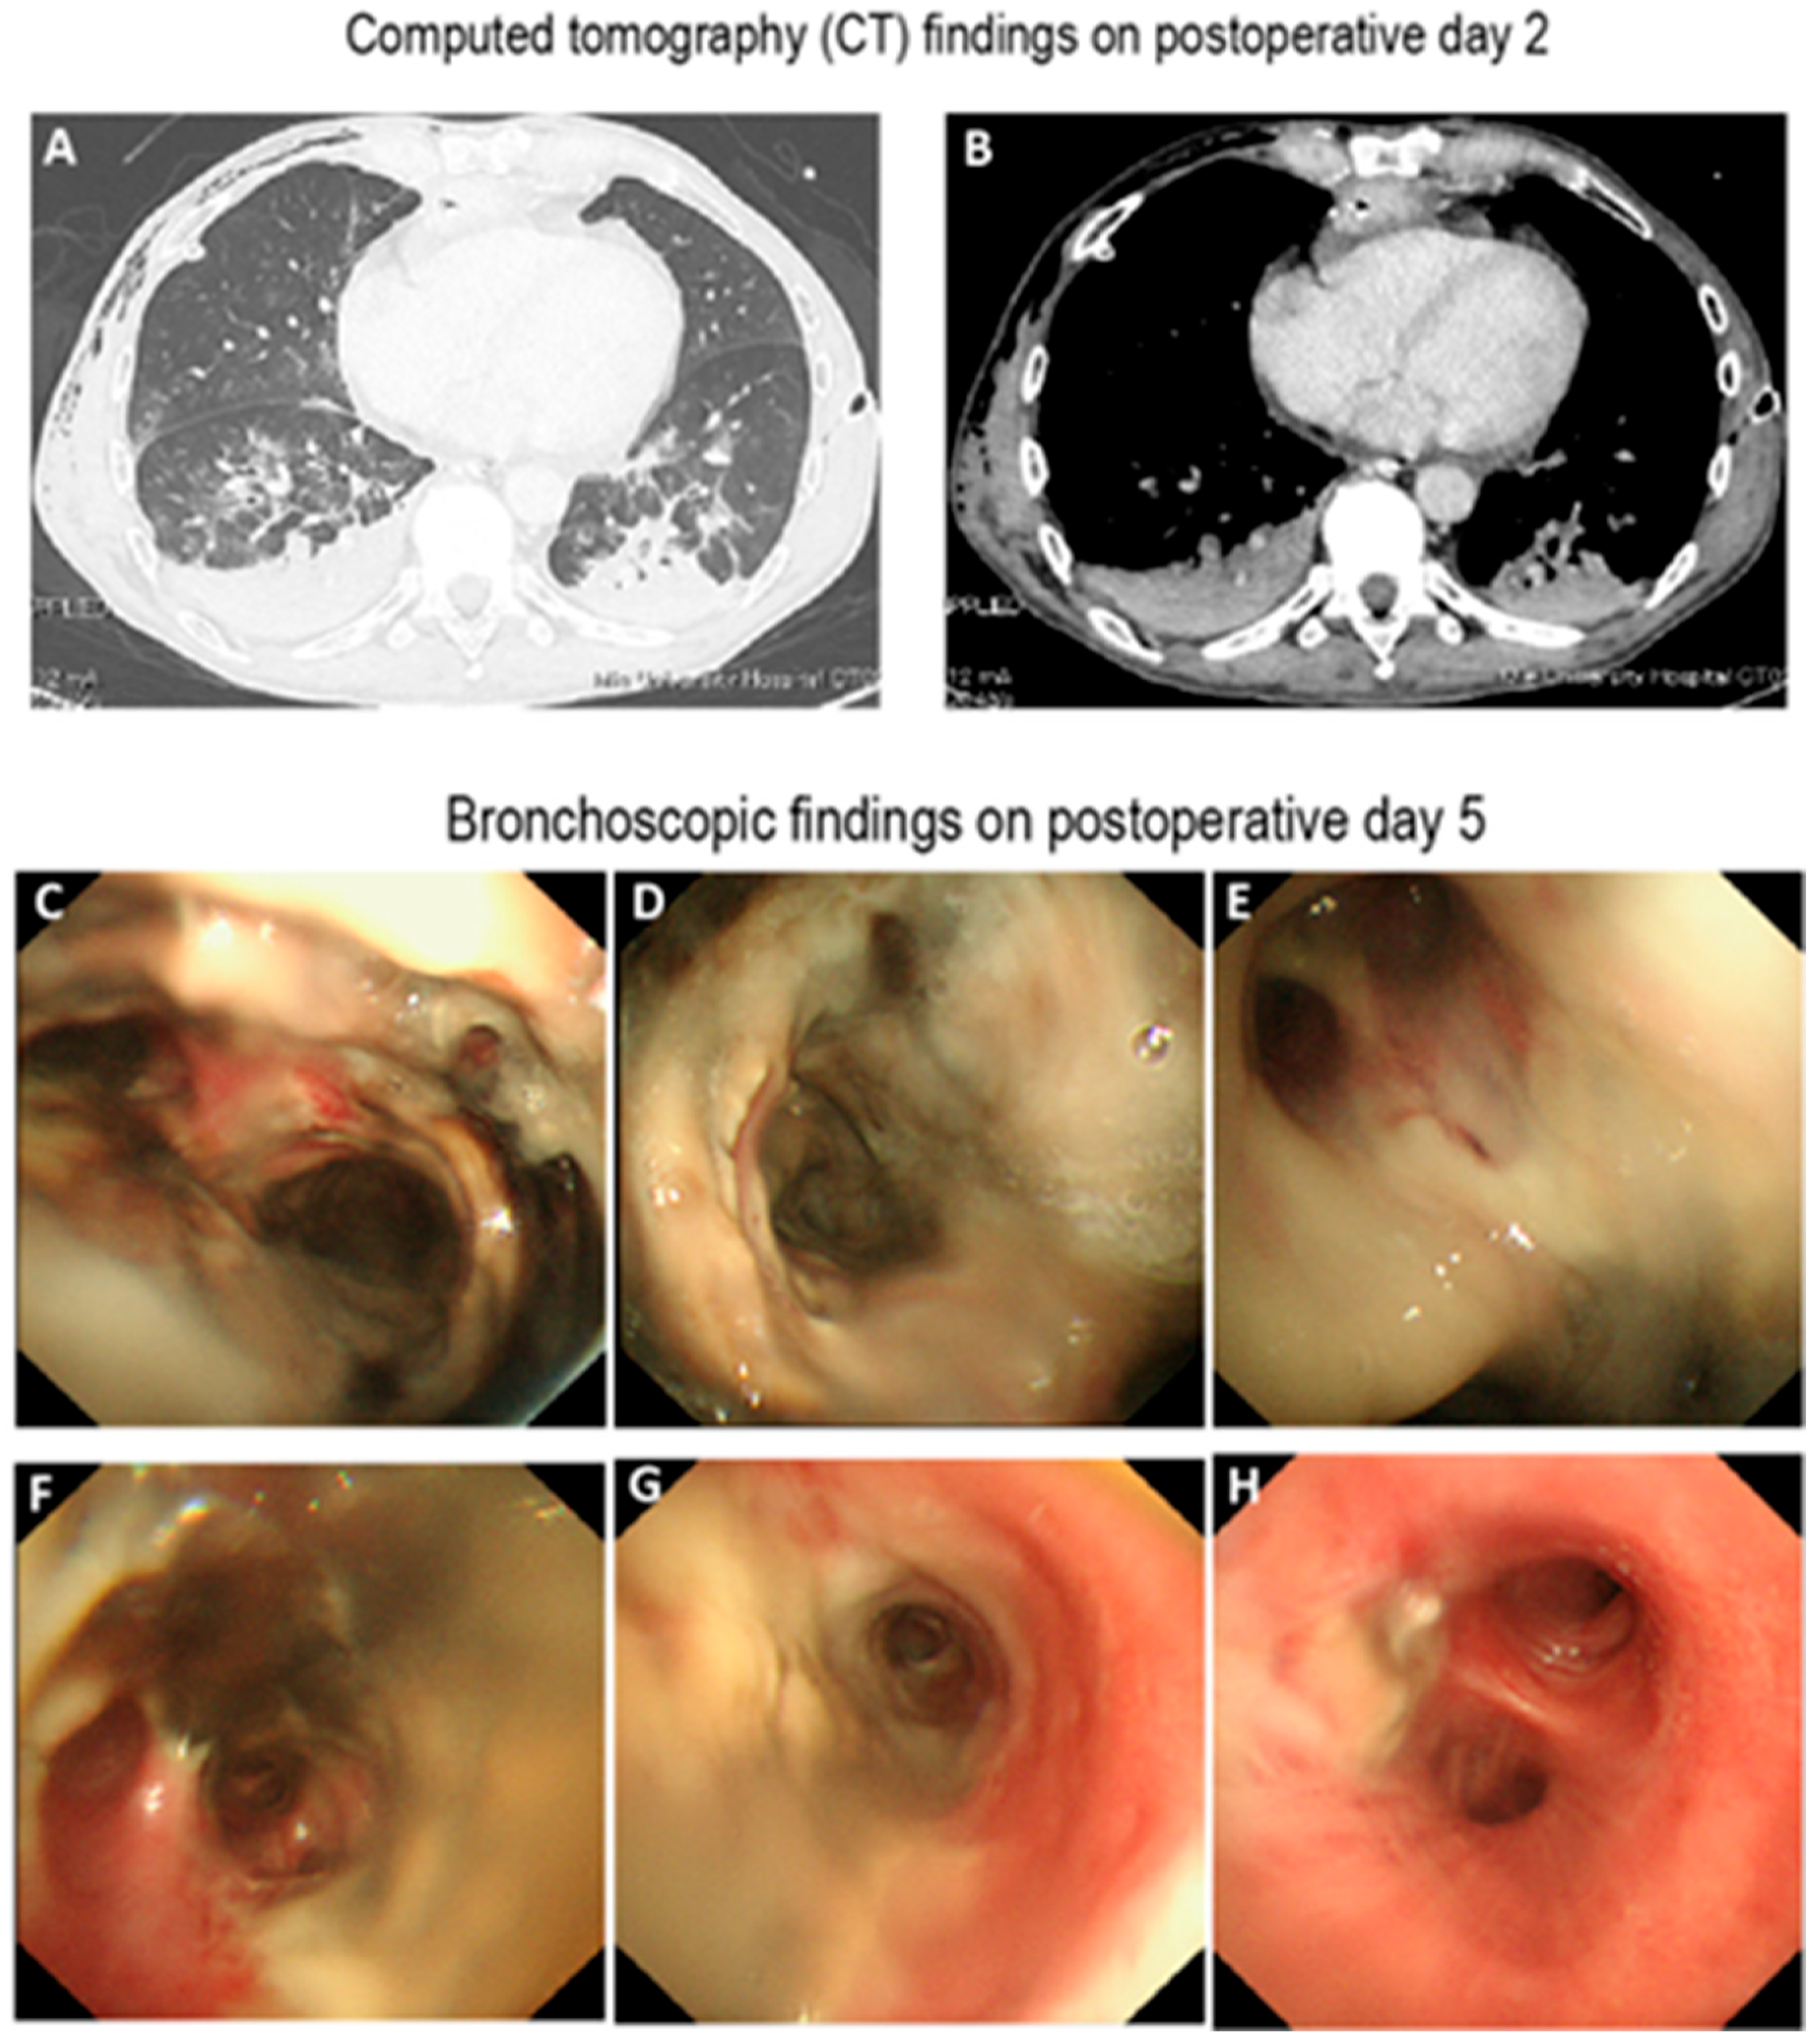

A Case of Extensive Airway Necrosis Following Esophagectomy Successfully Treated with Airway Stenting